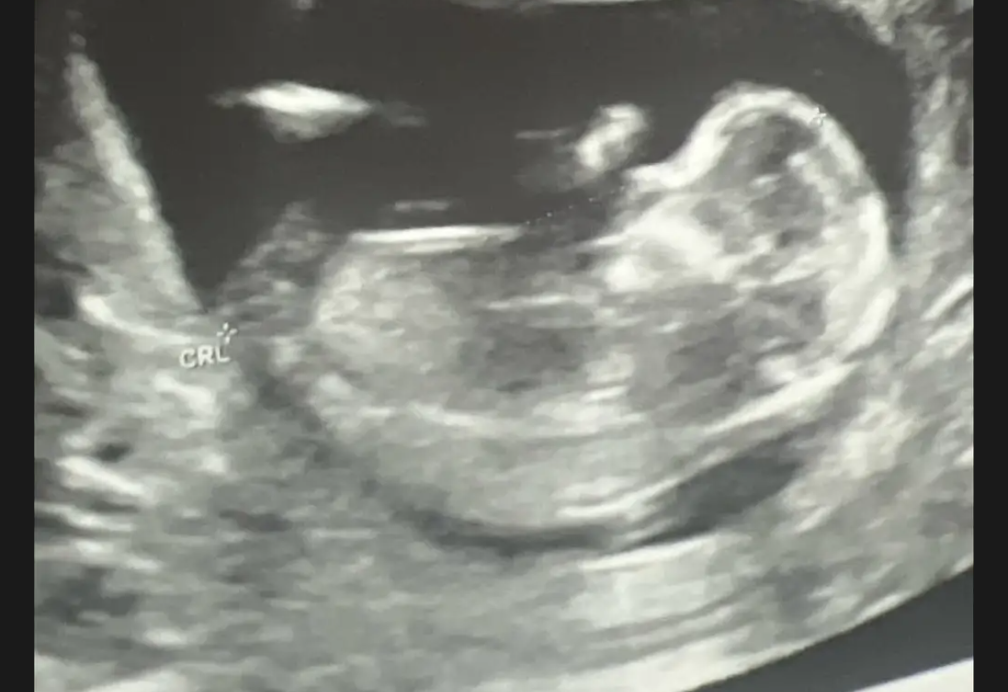

Ajo publikoi foto nga periudha e shtatzënisë, duke përfshirë ekon e foshnjës dhe barkun e rrumbullakosur, të cilat i shoqëroi me një dedikim që thyen zemra: “Heaven holds you now, but my heart holds you forever” (Parajsa të mban ty tani, por zemra ime do të të mbajë përgjithmonë).